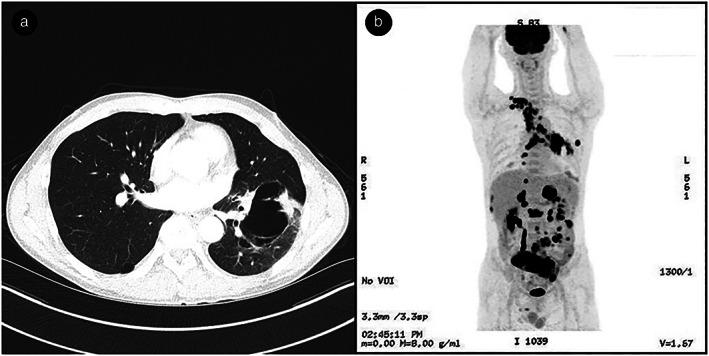

Here, we report a case of acute intestinal obstruction as the initial presentation of primary lung cancer in a male patient. Abdominal computed tomography (CT) showed multiple polypoid masses and regional lymphadenopathy with small bowel obstruction. The patient underwent emergency surgery for multiple luminal malignancy with mesenteric masses. According to the various clinicopathological features, the tumor was confirmed to be metastatic large cell carcinoma originating from the lung. Large masses in the left lower lobe of the lung were identified on the chest CT after emergency surgery, and non-small cell lung cancer (NSCLC), not otherwise specified (NOS), was finally diagnosed on biopsy through bronchoscopy.

在这里,我们报告了一例男性患者以急性肠梗阻为首发表现的原发性肺癌。腹部计算机断层扫描(CT)显示多发性息肉样肿块和区域性淋巴结病伴小肠梗阻。患者因多发性腔内恶性肿瘤和肠系膜肿块接受了紧急手术。根据各种临床病理特征,肿瘤被确认为源自肺部的转移性大细胞癌。急诊手术后胸部 CT 显示左肺下叶有大肿块,最终经支气管镜活检诊断为非小细胞肺癌(NSCLC),未特指。